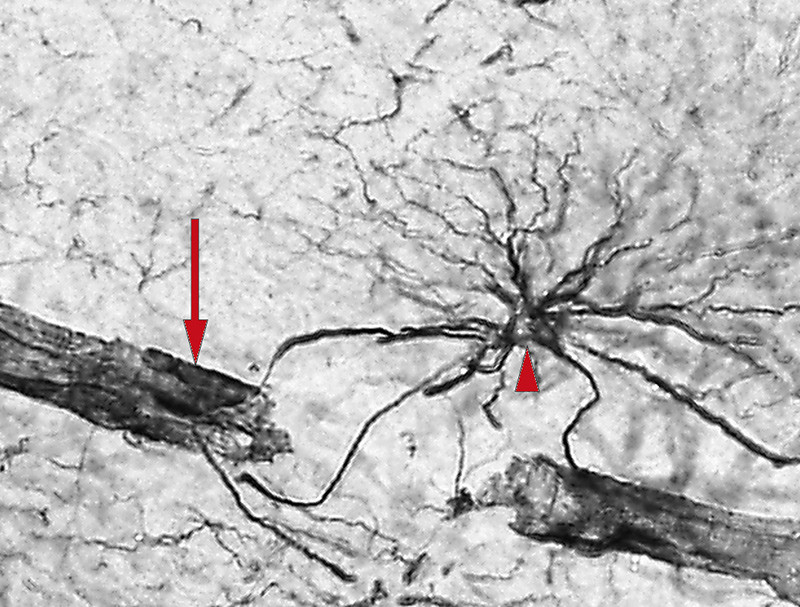

I motsetning til nerveceller er astrocytter koblet sammen i nettverk via kommunikasjonskanaler (gap junctions) (fig 1) (18). Disse er strukturer som skaper direkte forbindelser mellom cytoplasma til celler av samme type, noe som gjør at ulike molekyler og ioner kan passere direkte fra celle til celle. En rekke ioner, aminosyrer og andre substrater, blant annet K+, glutamat, adenosintrifosfat (ATP), Ca2+ og inositoltrifosfat (IP3) kan passere via disse kanalene fra astrocytt til astrocytt (19). For eksempel kan kalium på denne måten raskt omfordeles fra et miljø med høy til lav konsentrasjon. Også Ca2+, som er et viktig substrat for intracellulær signalformidling, kan via kommunikasjonskanaler raskt omfordeles og bidra til «informasjonsflyt» fra astrocytt til astrocytt. Dette prinsippet, som blir betegnet som Ca2+-signalering, utdypes i et senere avsnitt. Kobling mellom astrocytter muliggjør en rask omfordeling av overskudd av transmittere og ioner. Ny forskning tyder på at forstyrrelser i koblinger mellom astrocytter kan spille en rolle ved epilepsi (20).